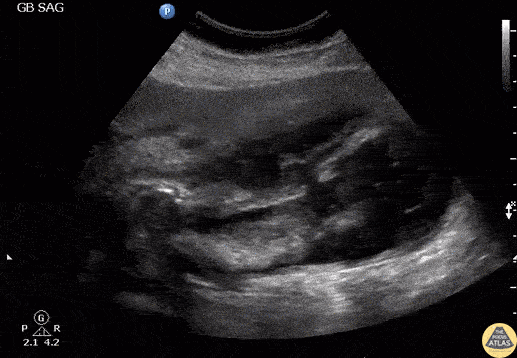

Patient presented with right upper quadrant abdominal pain and fever. RUQ ultrasound showed an impacted stone in the gallbladder neck with gallbladder wall perforation. Note the flow through the perforation and the associated pericholecystic abscess. Labelled image can be found on the original post with the link below. Image courtesy of Robert Jones DO, FACEP @RJonesSonoEM Director, Emergency Ultrasound; MetroHealth Medical Center; Professor, Case Western Reserve Medical School, Cleveland, OH View his original post here